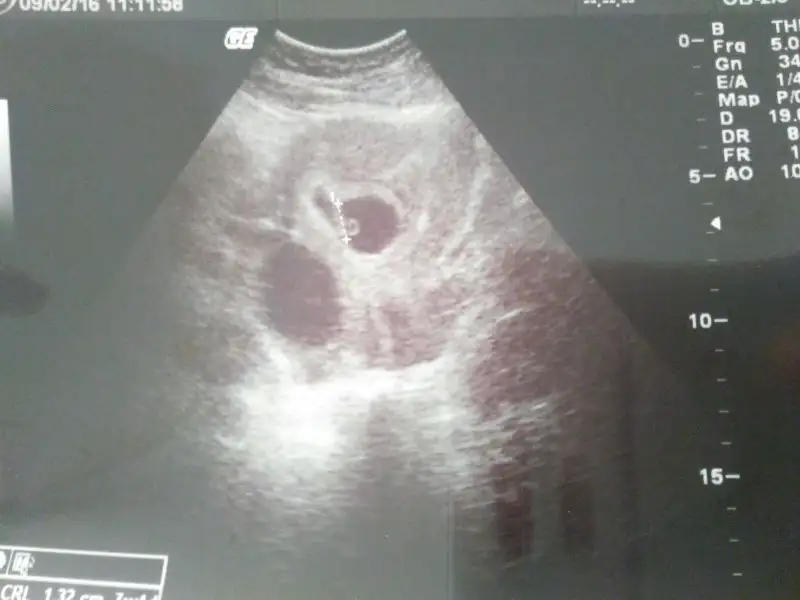

Plasentası sağda gözüküyor bu da gerçekte solda demektir. Ramzi teorisine göre kızı işaret eder. Allah sağlıkla kucağınıza almayı nasip eder inşallah

Plasenta solda görünüyor gerçekte sağda demktir bu erkek olma ihtimali yüksek olduğunu gösterir.Cnm bunun plesantasi nerde cinsiuet ne olabilir karindan bakilma 6 haftalik

Hayırl geceler ilk defa bu sayfayı takip etmeye başladım.Bana da yardımcı olsbilirmisiniz cinsiyetini öğrenmedik daha bilen arkadaşlar yardımcı olursanız cok mutlu olurum.13+4